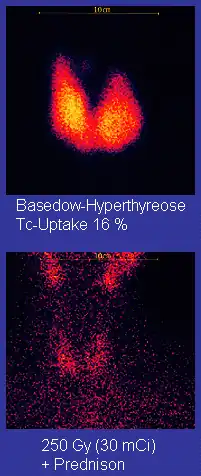

Beim Morbus Basedow ist das Ziel die dauerhafte Beseitigung der Überfunktion. Beim ablativen Therapiekonzept mit angestrebter Herddosis von 200 bis 300 Gray liegt die Erfolgsquote bei über 90 %. Allerdings sind anschließend 80 bis 90 % der Patienten dauerhaft von einer Substitution mit Schilddrüsenhormonen abhängig. Beim sogenannten funktionsoptimierten Konzept mit einer angestrebten Herddosis von etwa 150 Gray liegt die Rate an behandlungsbedürftigen Unterfunktionen zwar nur bei 40 %, allerdings die Erfolgsquote auch nur bei etwa 70 %. Insbesondere bei schwierigen Verläufen mit medikamentös nur schwer einstellbarer Überfunktion, Augenbeteiligung (endokrine Orbitopathie) oder wiederholten Rückfällen ist diese niedrige Erfolgsquote nicht akzeptabel, so dass inzwischen überwiegend das ablative Therapiekonzept angewendet wird. Für das alternative Behandlungsverfahren zur Radiojodtherapie, die Strumaresektion, ist ebenfalls regelhaft mit einer behandlungsbedürftigen Unterfunktion zu rechnen.[2]